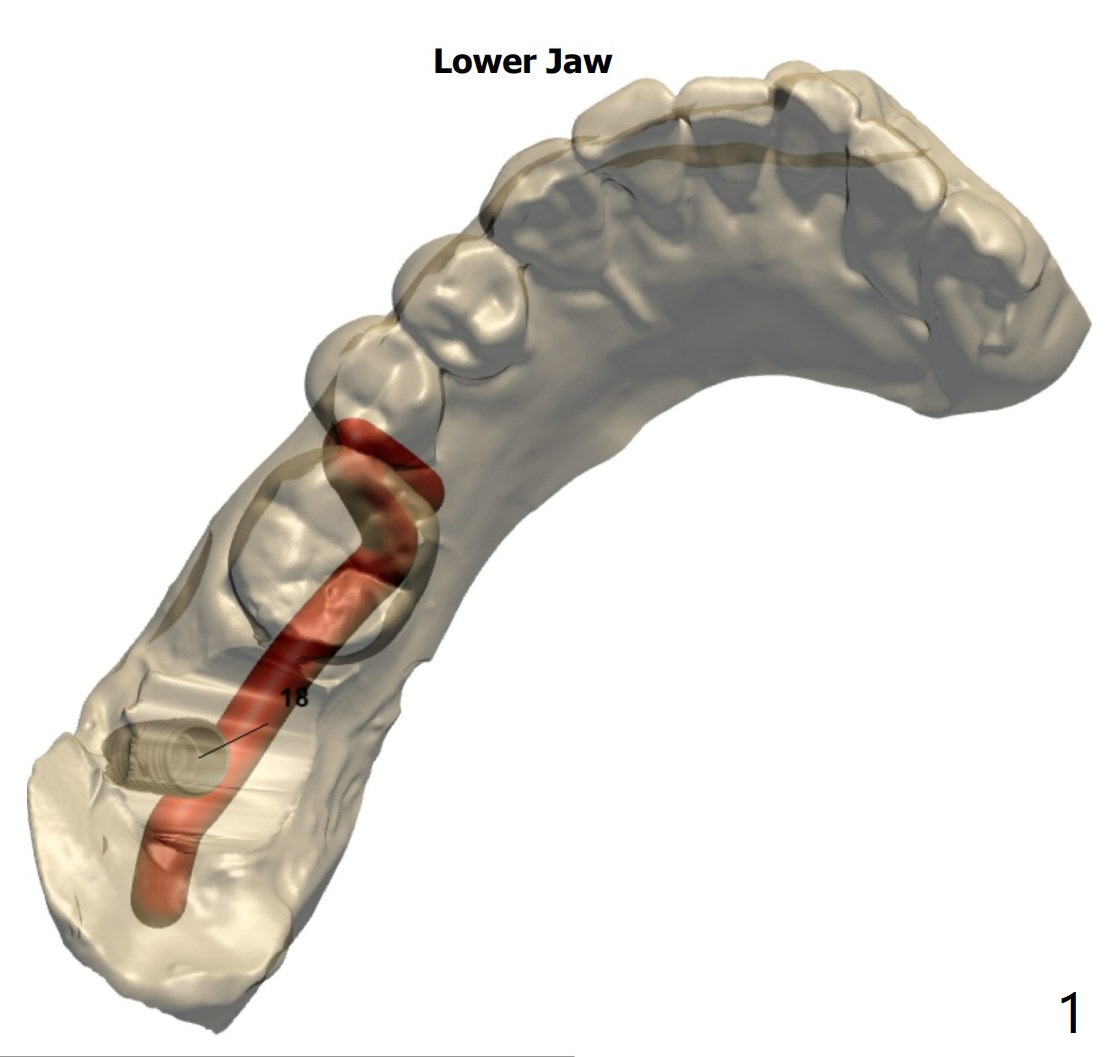

Bypass IAC/Angled Abutment